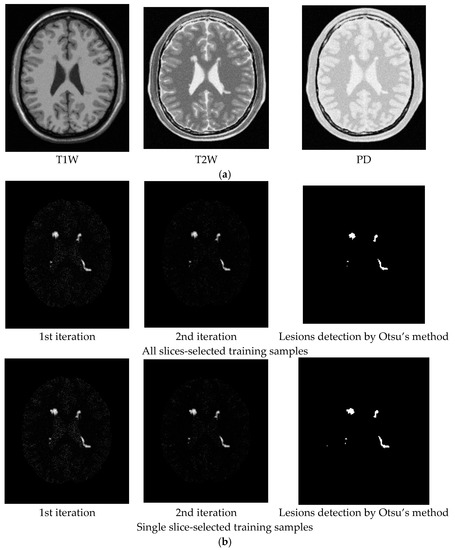

To conduct an objective quantitative study, the synthetic MR brain images containing multiple sclerosis (MS) lesions obtained from the MR imaging simulator of McGill University, Montreal, Canada were used for experiments [24]. MS lesions are typically hyperintense on T2W or FLAIR sequence image. Figure 4a–c shows a slice MR brain image along with the ground truth of MS lesion shown in Figure 4d. The MR brain images are acquired by the modalities of T1W, T2W and PD with specifications provided in BrainWeb site [24]. The thickness of slice is 1 mm with size of . Each slice is specified by INU (intensity non-uniformity) 0% or 20%, denoted by rf0 and rf20 with six different levels of noise, 0%, 1%, 3%, 5%, 7% and 9%. The noise in the background of the simulated images is simulated by Rayleigh statistics and signal regions are simulated by Rician statistics. The “percentage (%) of noise” represents the ratio of the standard deviation of the white Gaussian noise to the signal for a reference tissue [24] in terms of %. There were 23 MR images from 91 to 113 slices for our study. To implement ICEM, we need to know the desired target signature d. Two ways were suggested to select training samples to calculate d. One is called all slices-selected training samples, which selects a small set of training samples from all MR image slices. The other is called single slice-selected training samples, which selects a small set of training samples from a particular single MR image slice that can be further used to find training samples for entire MR image slices. Its idea was derived from the extrapolation process used in volume sphering analysis (VSA) developed in [14,15]. Table 1 specifies the values of parameters used for experiments where two Gaussian filters using window sizes of and , and two different σ = 0.1 and 0.5. The experiments were conducted for all MR image slices according to Table 1 where the results obtained by Gaussian window of with σ = 0.5 are tabulated in parentheses.

Figure 4.

Three MR images containing MS lesions acquired by T1W, T2W and PD with 0% noise and 0% INU. (a) T1W; (b) T2W; (c) PD; (d) ground truth (lesions)

For an illustrative purpose, Figure 5, Figure 6, Figure 7, Figure 8, Figure 9 and Figure 10 only show detection results of WMH lesions of the 97th MR image slice with six levels of noise and 0% INU by two versions of CBEP-ICEM, using the Gaussian window size of specified by σ = 0.1 and the Gaussian window size of specified by σ = 0.5, referred to as CBEP-ICEM1 and CBEP-ICEM2, respectively, where two sets of training samples selected by all slices and the single 102nd slice were used to calculate the desired target signatures d to implement NBE-ICEM. As we can see by visual inspection against the ground truth in Figure 4d, CBEP-ICEM1 and CBEP-ICEM2 using two sets of training samples, i.e., all slices-selected and single slice-selected training samples, produced very close results and they both also performed better lesion detection than LST did.

Lesion detection of Slice 97 with 0% noise and 0% INU by CBEP-ICEM1 and CBEP-ICEM2. (a) CBEP-ICEM1; (b) CBEP-ICEM2; (c) Lesion detection LST.